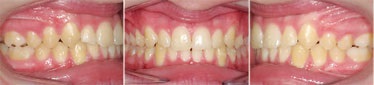

Figs. 3a-g: Initial records.

Fig. 3a

Fig. 3b

Fig. 3c

Fig. 3d

Fig. 3e

Fig. 3f

Fig. 3g